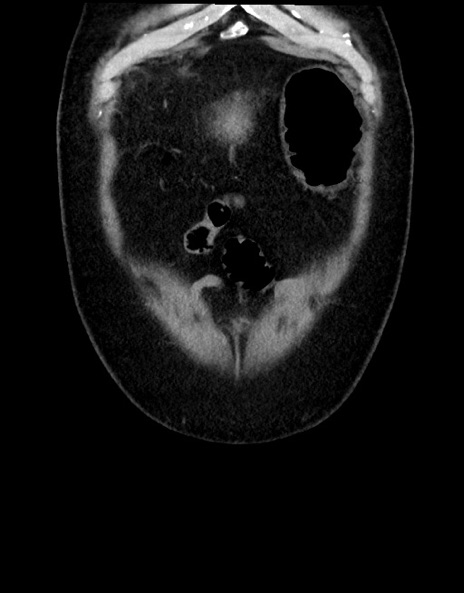

横断像

【症例】70歳代男性

【主訴】腹痛

【現病歴】今朝から腹痛あり。全体的に痛い。特に左上の方。排ガスが今日はない。冷や汗が出る。

【既往歴】直腸癌術後

【身体所見】左側腹部〜上腹部に圧痛あり。腹膜刺激症状明らかなではない。軽度反跳痛。左下腹部に術後瘢痕あり。

【データ】WBC 7700、CRP 0.02